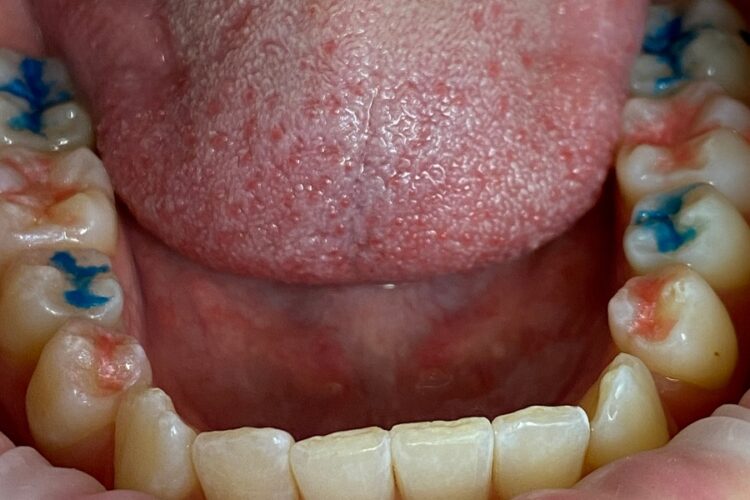

Sealing of fissures

Sealing of permanent teeth

Sealing of permanent teeth is used for both treatment of caries and prevention of its occurrence in children and adults.

Before sealing, it is important to remove dental plaque and tartar from the surface of the teeth.

The feature of the preparations used is not only in creating a mechanical barrier between microorganisms and the surface of the tooth, but also in the therapeutic effect, primarily bactericidal. In addition, they activate the own protective forces of tooth tissues, resulting in densification of the enamel in the fissure area.